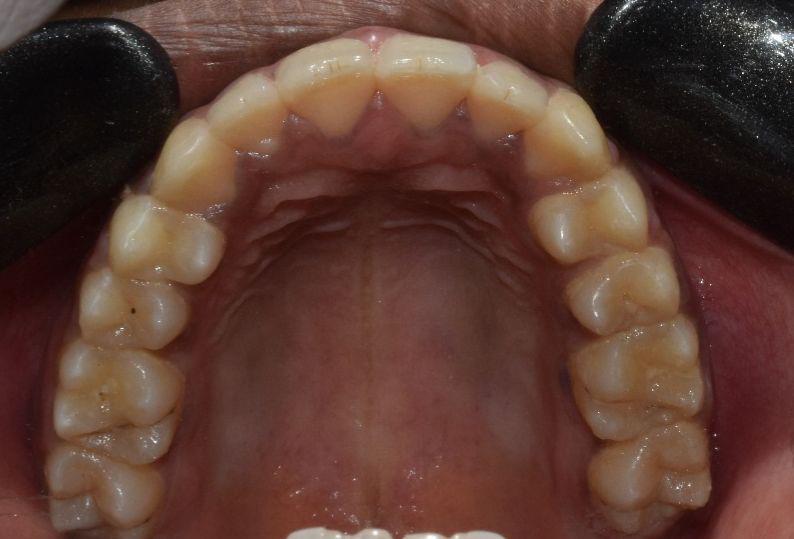

Before & After Results

At Aline Dent, we take pride in delivering visible and lasting improvements in our patients’ smiles. Our before-and-after results highlight the effectiveness of modern dental treatments combined with personalized care. This gallery showcases real dental cases treated at our clinic, giving you a clear idea of how different dental concerns can be corrected with the right treatment approach.

From minor corrections to complete smile enhancements, these teeth transformation results demonstrate how professional dental care can improve both oral health and appearance. Our experienced dental team carefully evaluates each patient’s needs and creates customized treatment plans to achieve natural, healthy, and confident smiles.

In this gallery, you will find a variety of smile makeover cases, including treatments for crooked teeth, gaps, discoloration, damaged teeth, and other common dental concerns.